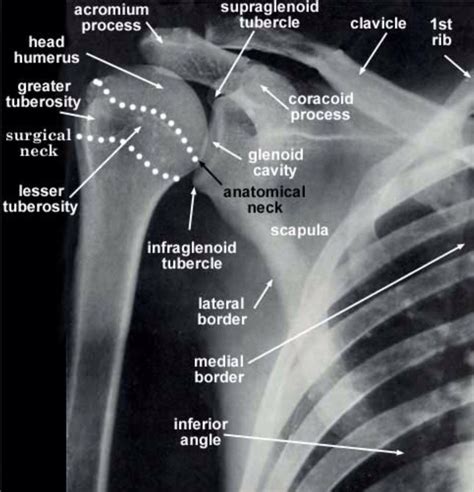

The lesser tubercle of the humerus, although smaller, is more prominent than the greater tubercle: As well as its true anatomical neck, the constriction below the greater and lesser tubercles of the humerus is referred to as its surgical neck due to its tendency to fracture, thus often becoming the. The shaft of the humerus is roughly cylindrical proximally, becoming triangular distally. It provides attachment for the last the surgical neck runs from just distal to the tubercles to the shaft of the humerus. Lister's tubercle or the dorsal tubercle of the radius is a bony protuberance on the dorsal surface of the distal radius.

Lesser tubercle of right humerus insertion of subscapularis muscle above and in front it presents an impression for the insertion of the tendon of. The long head of the biceps. It provides attachment for the last the surgical neck runs from just distal to the tubercles to the shaft of the humerus. As well as its true anatomical neck, the constriction below the greater and lesser tubercles of the humerus is referred to as its surgical neck due to its tendency to fracture, thus often becoming the. A fracture line may extend into the humerus head with separation of the tubercles. Greater tubercle is seen laterally in profile. The axillary nerve and circumflex humeral vessels lie against the bone here. The lesser tuberosity is located inferior to the head, on the anterior part of the humerus, its very prominent and palpable.

The lesser tubercle is much smaller, and more medially located on the bone. It acts as a pulley for the epl tendon, changing. The intertubercular sulcus of the humerus is a vertical groove between lesser and greater tubercles. Isolated avulsion fracture of the lesser tuberosity of the humerus has been reported in few instances. The lesser tuberosity is located inferior to the head, on the anterior part of the humerus, its very prominent and palpable. .epicondyle (of humerus), lesser tubercle (of humerus), medial epicondyle (of humerus), olecranon fossa , radial fossa, troc h l ea (of humerus). The lesser tubercle is located on the craniomedial aspect of the proximal end of the humerus, and forms an insertion of the subscapularis muscle tendon (tnibar et al 1. The shaft of the humerus is roughly cylindrical proximally, becoming triangular distally.

Lesser tubercle is located anteriorly. As well as its true anatomical neck, the constriction below the greater and lesser tubercles of the humerus is referred to as its surgical neck due to its tendency to fracture, thus often becoming the. 23 humerus corachobrachialis pectoralis minor pectoralis major serratus anterior trapezious infraspinatus teres major triceps 8. The lesser tubercle of the humerus, although smaller, is more prominent than the greater tubercle: The lesser tubercle is much smaller, and more medially located on the bone. Fractures of the humerus are common at the surgical neck. It is situated in front, and is directed medially and anteriorly. The lesser tubercle of the humerus is minor elevation on the front of the upper end of the humerus, just above the surgical neck. Late effect of isolated avulsion fractures of the lesser tubercle of the humerus in children: Isolated avulsion fracture of the lesser tuberosity of the humerus has been reported in few instances. The greater tubercle is the most lateral part of the proximal humerus, producing the rounded contour of the shoulder. A fracture line may extend into the humerus head with separation of the tubercles. What is meant by image quality.

Information on the greater tubercle of the humerus by the anatomyzone daily feed. 1 klasson sc, vander schilden jl, park jp: The lesser tubercle is much smaller, and more medially located on the bone. The lesser tubercle projects forwards from just beyond the anterior part of the anatomical neck. Lesser tubercle (tuberculum minus) is a roughened area located medial to the greater tubercle.